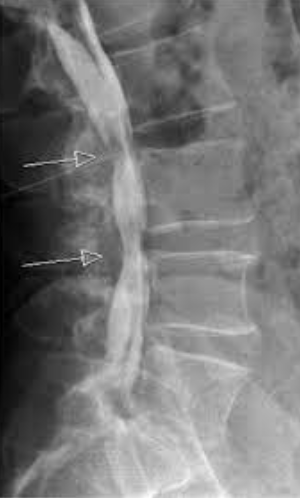

방사선 검사(X-ray): 척추뼈의 퇴행성 변화, 척추 전위 등 구조적 이상을 확인한다.

척수 조영술: 필요에 따라 시행, 척추관 내 조영제가 좁아진 모습 등 협착 소견 확인.